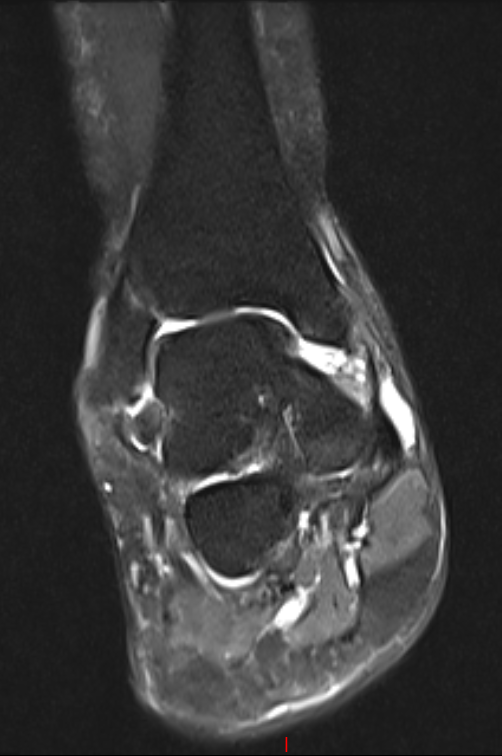

第二位是54岁的大哥,“脚脖子”痛了3年,检查发现只有部分距骨出了问题。

术前磁共振

针对这种局部病变,团队用了3D打印部分距骨置换术。

这种手术不用大动,只换病变的那部分距骨,尽量保住健康的关节组织,创伤小,术后恢复起来也能快一点。